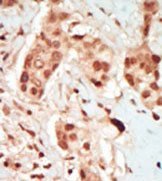

Supportive validation

- Submitted by

- antibodies-online (provider)

- Main image

- Experimental details

- IHC